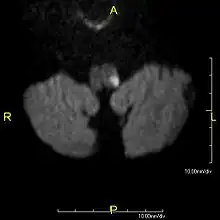

a)High signal in left postero lateral indicates a infarct and thrombosed left vertebral artery b) infarct (circle ) c)indicates absence of normal left vertebral artery ( circle ) -

Clinical B1000 diffusion weighted MRI image showing an acute left sided dorsal lateral medullary infarct -